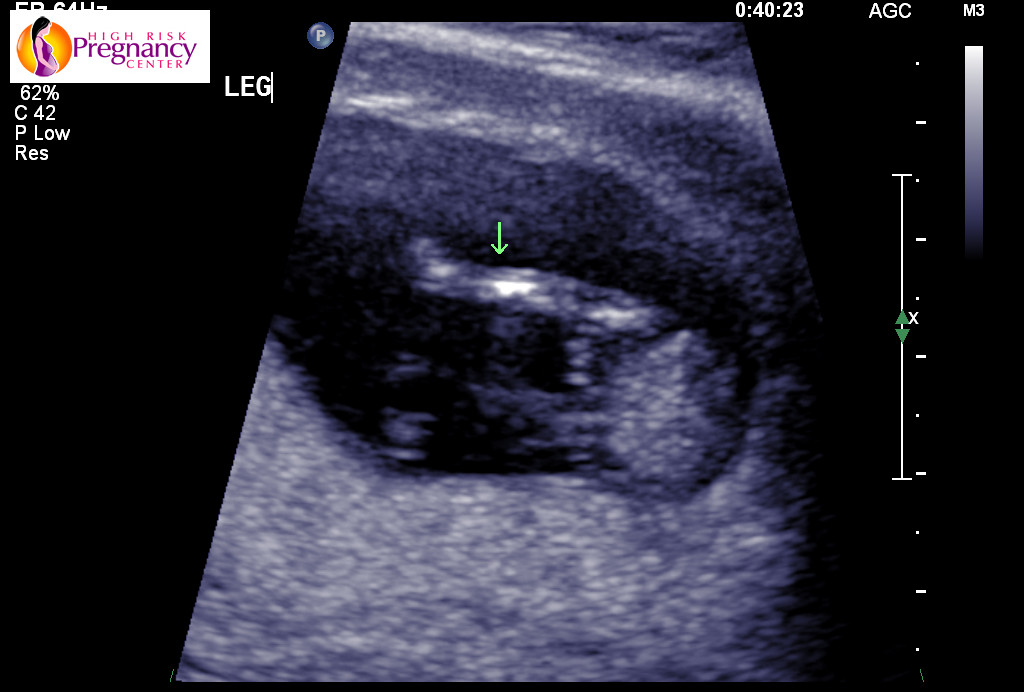

Attachment 21251

Potty shots are no good at all at this stage due to male and females having the same nub. Looking at the second pic I would lean boy seems the nub has lines above it that look stacked but could be cord so could just as easily hear girl too x